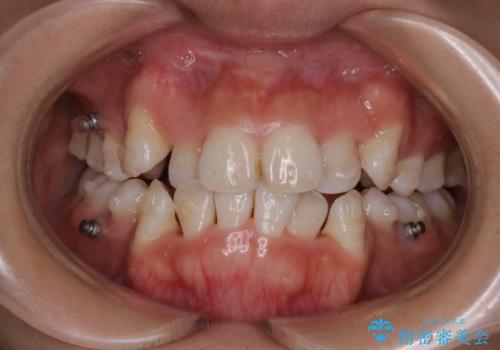

インビザライン単独での抜歯矯正治療

- 当院にてインビザライン治療を行っていた同僚の方からのご紹介でいらした方です。楽器を演奏されるとの事で、インビザラインによる矯正治療をご希望されました。治療の途中で一時的にワイヤー矯正に切り替える可能性もあることもご了承頂いた上で治療を行いました。

1日20時間以上、正しくインビザラインを使用して頂いたおかげで、ワイヤーに切り替えることなく矯正治療を終了することが出来ました。抜歯症例でしたが比較的短期間で見た目が劇的に改善し、大変喜んでいただけました。